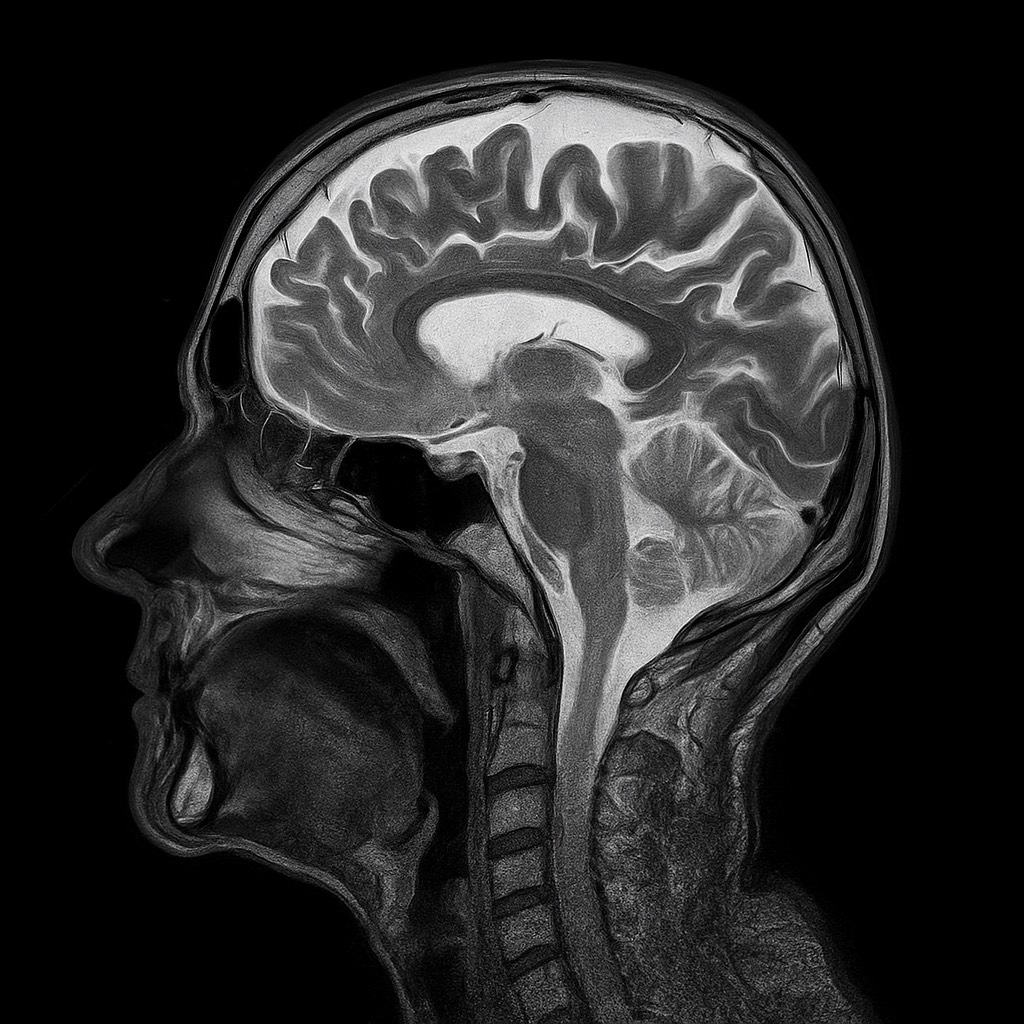

Le cerveau ado : fragile… ou surpuissant ?

Vif, curieux, capable d’apprendre à toute vitesse… mais aussi sensible et parfois débordé. Découvrez les secrets d’un cerveau en pleine effervescence !